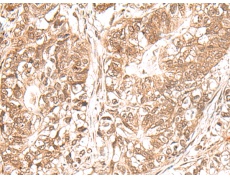

ELISA, IHC

IHC positive control:

Human gastric cancer and Human ovarian cancer

IHC Recommend dilution:

30-150